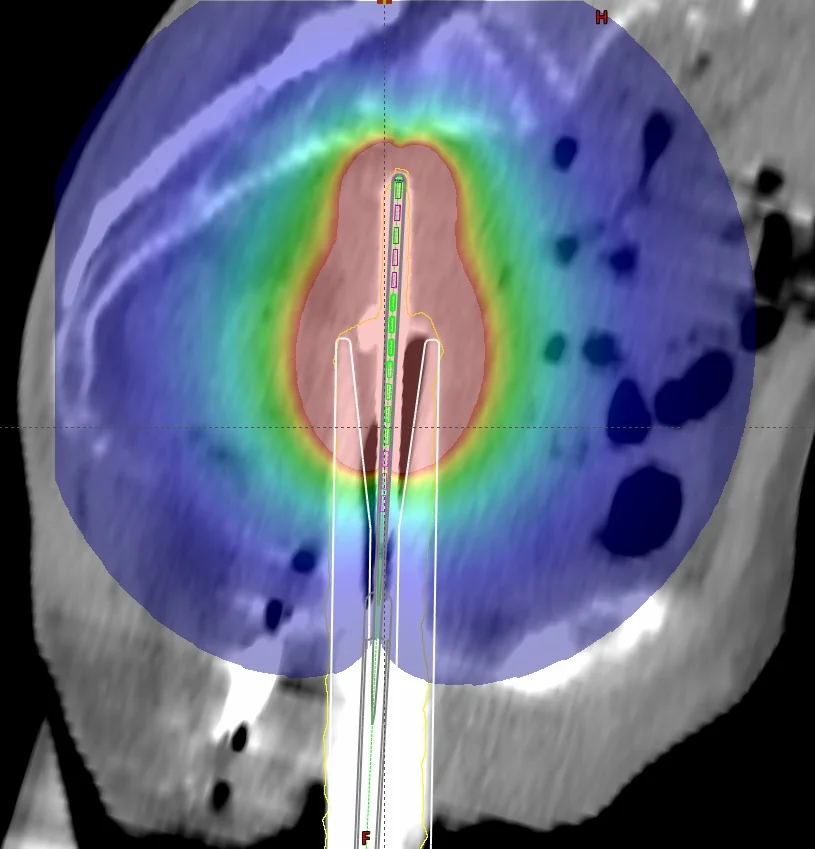

Der MammoSite-Applikator ist ein füllbarer sphärischer Silikonballon, der intraoperativ in der Kavität des entfernten Tumors platziert wird. Der wird Ballon wird mit einem Gemisch aus isotoner Kochsalzlösung 0,9 % und Kontrastmittel (z. B. in einem Verhältnis von 10:1) gefüllt. Das iodhaltige Kontrastmittel hebt den Ballon auf den CT-Bildern vom Brustgewebe ab, sodass er für die Bestrahlungsplanung gut konturiert werden kann. Eine zu hohe Kontrastmittelkonzentration (Empfehlung: <10 %) kann bei Berechnungen mithilfe des TG-43-Algorithmus, der zur Berechnung eine reine Wasserumgebung annimmt, zu großen Dosisabweichungen führen. Das liegt vor allem an dem hohen Iodgehalt in den Kontrastmittellösungen, das aufgrund seiner hohen Dichte zu Dosisreduzierungen führen kann, die vom TG-43-Algorithmus nicht berücksichtigt werden. In mehreren Sitzungen wird die Quelle durch einen Zweikanal-Katheter in den Ballon gefahren. Der Durchmesser des Ballons variiert je nach Patient und Ausführung des Ballons. Um den hohen Ansprüchen komplexer Dosisverteilungen gerecht zu werden, gibt es seit einiger Zeit Multilumen-Varianten (nicht sehr verbreitet in Deutschland), die unter Verwendung mehrerer Katheter weitere Haltepositionen ermöglichen.

Nach der chirurgischen Entfernung des Tumors, wird der MammoSite-Applikator eingesetzt und verweilt dort für die gesamte Behandlungszeit (ca. eine Woche). Am zweiten Tag wird ein Planungs-CT gefahren und basierend auf der Anweisung ein Bestrahlungsplan erstellt. In den letzten drei Tagen wird in je zwei Sitzungen pro Tag eine Dosis in einem bestimmten Abstand, in der Regel in 0,5 cm Gewebstiefe bzw. 0,5 cm von der Ballonoberfläche appliziert. Die Haut- und Rippendosis sollten eine Maximaldosis (z. B. 1,5 Gy pro Fraktion) nicht überschreiten, und bilden somit die limitierenden Faktoren der Behandlung. Je nach klinischer Erfahrung, variieren die Dosierungskonzepte und tolerierbaren Maximaldosen in den Risikoorganen.

Sofern in der Computertomographie um den Ballon große Lufteinschlüsse zu sehen sind (z. B. weil die Kavität das maximale Ballonvolumen überschreitet, oder dieser nicht vollständig aufgefüllt wurde) müssen diese ebenfalls berücksichtigt werden, da Dichteinhomogenitäten vom am weitesten verbreiteten TG-43-Algorithmus nicht berücksichtigt werden. Zu diesem bekannten Problem existiert bereits eine Reihe von Publikationen. Diese beschäftigen sich überwiegend mit den Auswirkungen vom Kontrastmittel, von Lufteinschlüssen am und im Ballon und mit dem Umgebungsmedium, dass im TG-43-Formalismus als Wasser angenommen wird, woraus eine erhöhte Rückstreuung resultiert.